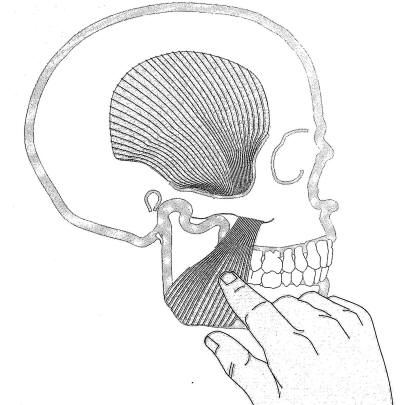

Palpación del músculo masetero: |

La palpación del músculo masetero no presenta

inconvenientes, con una presión moderada en apertura y

cierre podremos determinar el grado de dolor que presenta el

paciente y el trismus presente. |